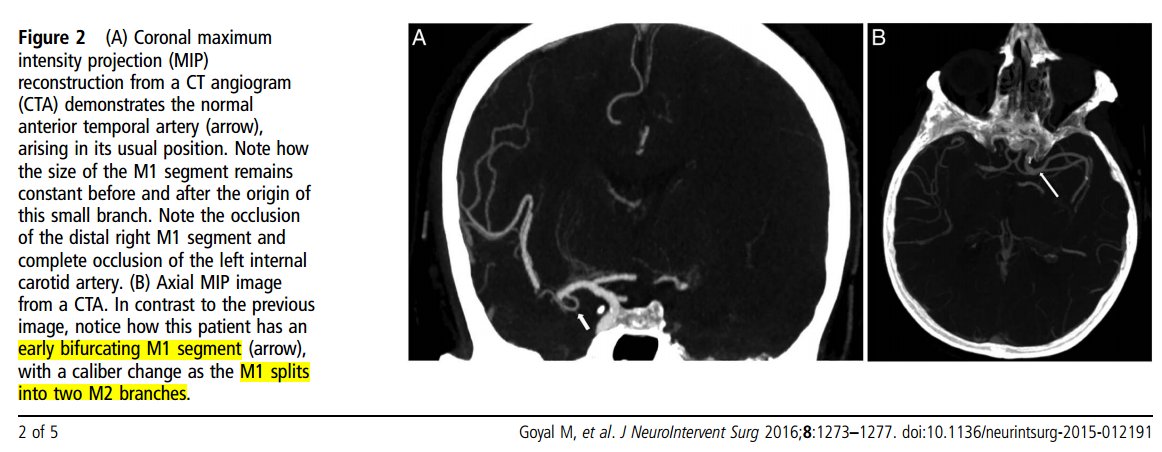

Where does the middle cerebral artery M1 segment become the M2 segment?

By genu, I mean where the vessel turns from coursing horizontally/laterally to coursing vertically/posteriorly, around the limen insulae. The bifurcation is classically at this point but in reality usually occurs proximal or distal to this point.

The bifurcation-based approach has been supported by some stroke expert group statements doi.org doi.org

In the DAWN trial, an inclusion criterion was ICA or MCA-M1 occlusion. M1-M2 junction was defined by the bifurcation. Some probably didn't get the memo: there were 5 patients enrolled (out of 206) that the core lab judged to actually have M2 occlusions. doi.org